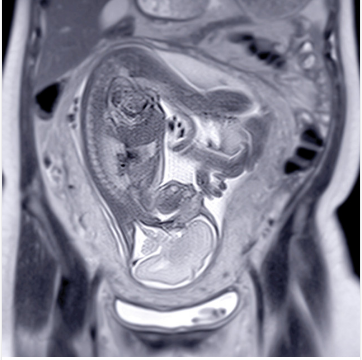

This online women’s ObGyn imaging CME program is designed to strengthen your diagnostic imaging skills, enhance your clinical practice, and deepen your knowledge of many current issues in gynecologic and fetal imaging.

Core concepts, practical applications, appropriate indications, and diagnostic pearls are highlighted in the UCSF ObGyn Women’s Imaging continuing medical education course, with emphasis on timely and accurate diagnoses and impact on outcome. Expert speakers address future directions and controversial topics, as well as maternofetal medicine, infertility, O-RADS, postmenopausal bleeding, endometriosis, high-risk pregnancy, infertility, first trimester lexicon terminology, performance standards, and benign/malignant/emergency gynecologic conditions.